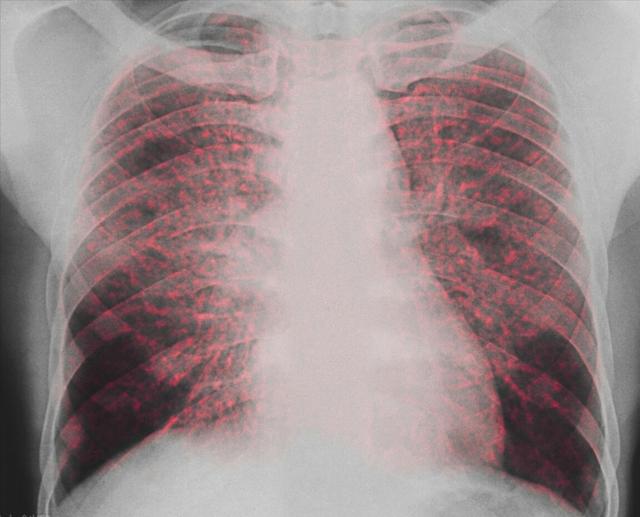

Can A Benign Lung Nodule Become Cancerous . Doubling time <30 days usually represents an acute infection. But it’s possible for a benign lung nodule to become malignant over time. Lung nodules (pulmonary nodules) and benign lung tumors, are not cancerous, but can still have serious health and respiratory. Most lung nodules aren't cancer, but a careful review of the patient's risks and a nodule's characteristics is important to identify. Doubling time >450 days indicates a benign nodule. Most small lung nodules are benign and won’t ever become cancerous. A malignant nodule is more likely to. The exact incidence of benign lung tumors is uncertain and may vary by what is classified as a lung tumor. A ct scan usually isn't enough to tell whether a lung lesion is a benign tumor or a cancerous lump. Can a ct scan tell if a lung nodule is cancerous? The short answer is no. However, it’s important to follow screening guidelines to ensure that a malignant nodule is detected and treated in its early stages. Most lung nodules are benign. For example, there are conditions other than benign and malignant lung tumors that may appear as a nodule on imaging studies.